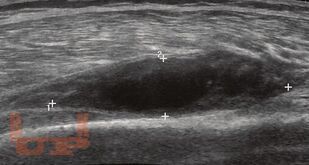

Учебное пособие предназначено для студентов лечебного, стоматологического и педиатрического факультетов, ординаторов для углубленного изучения основ хирургии, а также для врачей практического здравоохранения. В пособии дано представление о хирургической инфекции, основных актах, регулирующих правила профилактики и лечения внутрибольничной инфекции, основных видах хирургической инфекции, методах и принципах диагностики и лечения.